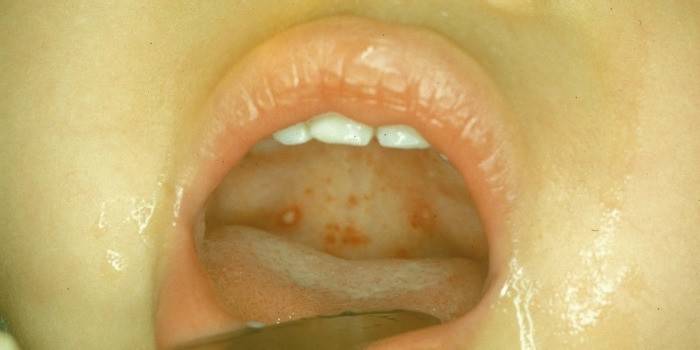

- purulentný biely plak alebo hnisové uzliny s léziami mandlí;

- bolesti hlavy, nepríjemné pocity v hrdle po požití.

Fotografie hnisavého bolesti v krku